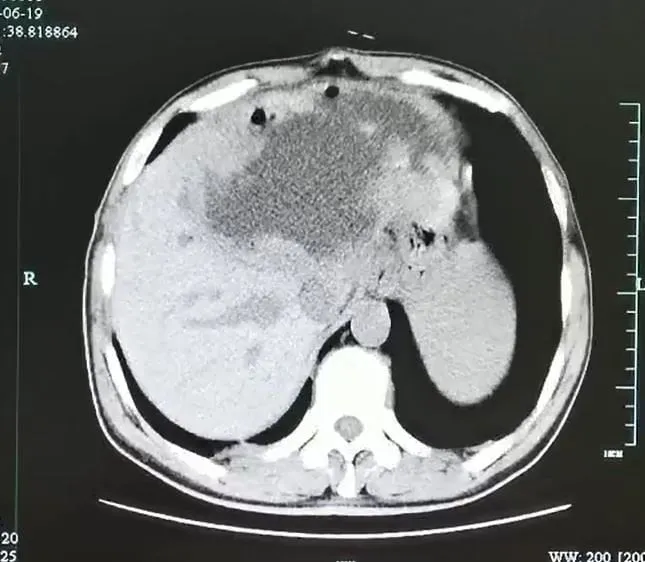

Le foie avant le drainage

1/4

Service de presse

L'énorme abcès du foie avant drainage. L'hôpital précise que plusieurs des structures visibles ressemblaient à des tumeurs.